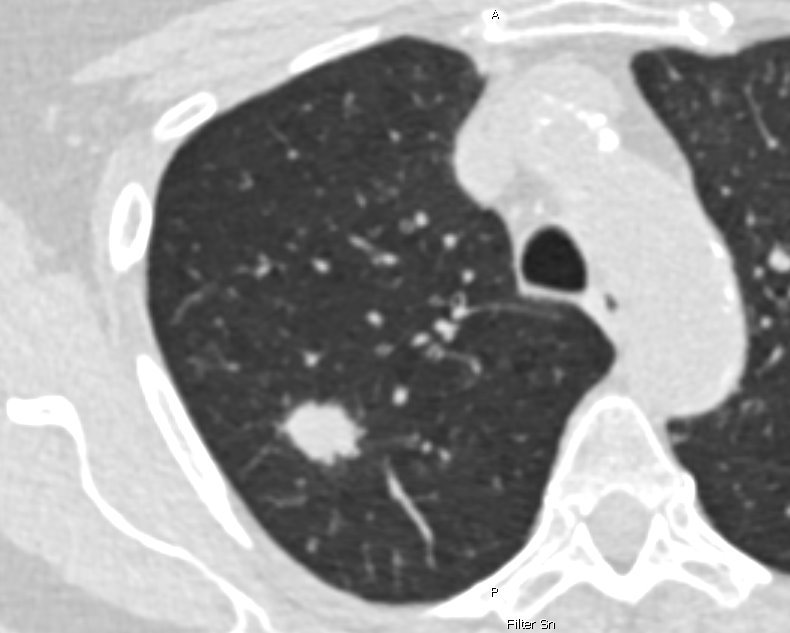

Jedes Jahr wird in Deutschland bei rund 57.000 Menschen Lungenkrebs diagnostiziert – mit oft tödlichem Ausgang, weil die Erkrankung typischerweise zu spät entdeckt wird. Voraussichtlich ab April 2026 soll ein neues Früherkennungsprogramm starten, das bei Menschen mit hohem Lungenkrebsrisiko mittels Computertomografie (CT) überprüft, ob verdächtige Veränderungen der Lunge vorliegen. Bisher ist geplant, dass das Lungenkrebs-Screening Personen zwischen 50 und 75 Jahren angeboten wird, die – vereinfacht gesagt – über 25 Jahre stark geraucht haben.

Die im Rahmen des Deutschen Zentrums für Lungenforschung (DZL) entstandene Studie untersuchte, wie gut ein CT-Screening Lungenkrebs frühzeitig erkennt, wenn man die Teilnehmenden nach einem umfassenden Kriterienkatalog, dem sogenannten PLCOm2012-Score, auswählt. Er berücksichtigt neben dem Alter und der Rauchhistorie einer Person auch ihren Bildungsstand, das Gewicht, das Vorliegen einer chronisch-obstruktiven Lungenerkrankung (COPD), vergangene Krebserkrankungen und ob es in der Familie Lungenkrebsfälle gegeben hat.

Verglichen wurden die Ergebnisse mit den Auswahlkriterien, die dem geplanten Lungenkrebs-Screening zugrunde liegen sollen und die ausschließlich das Alter und die Rauchhistorie berücksichtigen („NELSON-Score“). Alle Personen, denen anhand einer der beiden Scores ein hohes Lungenkrebsrisiko attestiert wurde, erhielten im Rahmen der Studie im Abstand von einem Jahr zweimal ein Niedrigdosis-CT. Verdachtsfälle wurden in interdisziplinären Fallkonferenzen überprüft und bei Bestätigung eine Behandlung eingeleitet.